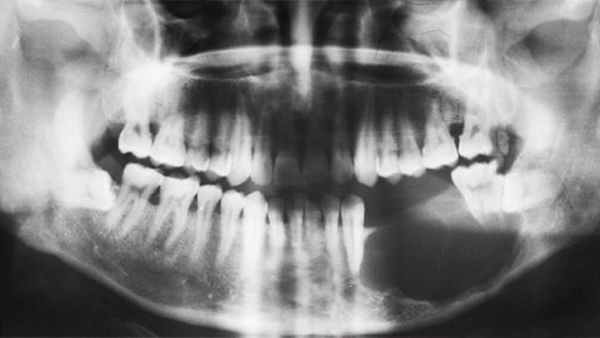

Рентгенологическая картина

Возможны следующие варианты амелобластомы:

1. Ряд округлых полостей.

2. Одна костная полость, окруженная множеством более мелких полостей.

3. Ряд округлых полостей, в 1-2 из которых заключен зубной фолликул или сформированный зуб.

4. Многоугольные полости.

5. Крупнопетлистая структура кости за счет множества мелких кист.

6. Несколько единичных крупных кистозных полостей.

7. Одна большая кистозная полость с неровными краями.

8. Одна большая полость, в которую обращены корни зубов (напоминает радикулярную кисту).

9. Одна большая киста, в которую обращена коронковая часть непрорезавшегося зуба. Этот вариант напоминает фолликулярную кисту.

Важнейшей рентгенологической чертой адамантином является различная степень прозрачности тени полостей особенно четко выраженной в поликистозных адамантиномах. Центральные отделы кистозных полостей прозрачнее, чем краевые. В однокамерных адамантиномах удается видеть полоску полутени вдоль костных границ опухоли. Нередко отмечается резорбция корней зубов в области опухоли.